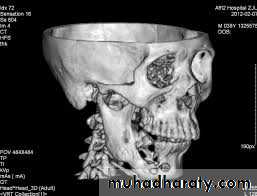

Radiographical appearance ;

It is possible to see a patient with acute osteomyelitis that has a normal-appearing orthopantomogram. However, one can often see the appearance of "moth-eaten" bone or sequestrum of bone, which is the classic appearance of osteomyelitis.14

Computerized tomography (CT) scans have become the standard in evaluating maxillofacial pathology such as osteomyelitis. its sensitive in late stage when 30%-50% of the bone demineralized.